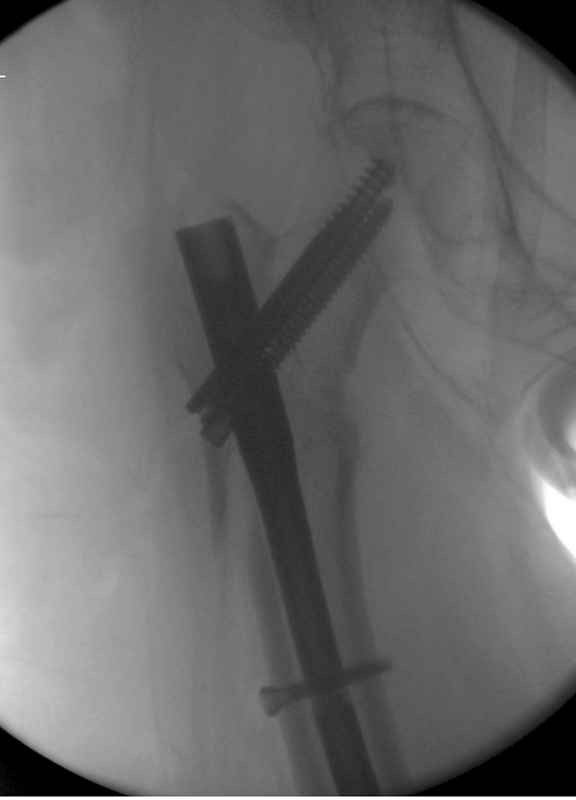

Здесь пара случаев фиксации похожих переломов:

первый высокоэнергетическая травма 36 лет

Здесь 83 года, травма в результате падения